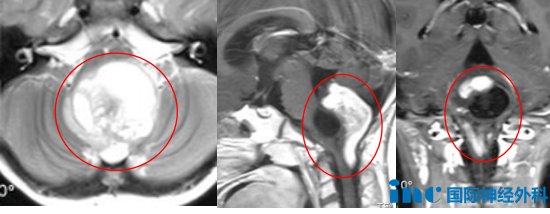

游泳?满满母亲遂带领6岁的女儿开始学习游泳,无人预料到,这个看似平常的决定,竟会引向文章开头所述那令人心悸的一幕。当然,意外事件通常由多重因素交织导致,难以归咎于单一原因。所有问题的根源,或许均源于这个颅内肿瘤。思及此处,满满母亲内心犹如被千万根针刺般疼痛。头颅磁共振成像(MRI)发现:第四脑室下方-枕大孔区-上段颈椎椎管偏后部存在占位性病变:考虑星形细胞瘤?室管膜瘤?幕上脑积水;颈髓内可见异常信号:脊髓中央管可能增宽?

手术的核心难点在于,肿瘤侵犯了生命中枢的核心区域——脑干,并且向小脑及颅颈交界区广泛侵袭。该区域掌管着呼吸、心跳、意识等基本生命功能,且被密集的神经血管网络包绕,手术操作空间以毫米计。任何细微的偏差,均可能导致不可逆的神经功能损伤,甚至危及生命。

这台高难度手术由INC巴特朗菲教授主刀,苏州大学附属儿童医院神经外科团队密切配合,成功为满满安全切除了肿瘤!术后病理学检查结果为节细胞胶质瘤,Ki67指数为10%。令人欣慰的是,术后满满的所有症状——呛咳、呕吐、伸舌右偏均已消失,且未出现任何新发的神经功能损伤。从重症监护病房(ICU)转回普通病房后,她恢复进程十分顺利,精神状态日益好转。不到两周,这位勇敢的小女孩便顺利出院,重新沐浴在阳光之下。有时,战胜疾病的不仅仅是医疗技术,更是一个家庭永不放弃的信念,以及那份倾尽全力的托举。此类医疗成功的案例,在巴特朗菲教授的治疗经历中并非偶然。2026年3月中下旬,巴特朗菲教授将再次来访中国,为包括脑干肿瘤在内的复杂病例患儿家庭,带来重获新生的希望。INC巴教授3月行程公布!疑难脑瘤患者为何坚持等待这位德国神经外科专家?